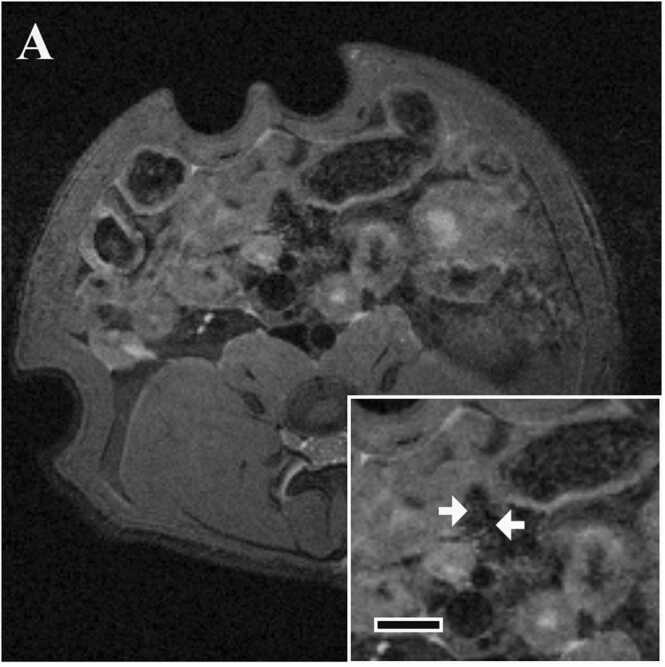

No high signal intensity region was observed around the mesenteric artery in any animal (Fig. 4).

Fig. 4.

Typical images of MRI of mesenteric arteries in Experiment 2 (in vivo MRI 7 days after the final dose and histopathology). Axial image in the MH group 7 days after administration of the final dose. Inserts show cross section of the mesenteric artery at higher magnification. Bar in insert, 3 mm. There is no high signal intensity region. Arteries are indicated by arrows.

3.2.3.2. Experiment 2 (in vivo MRI on 7 days after the final dosing and histopathology)